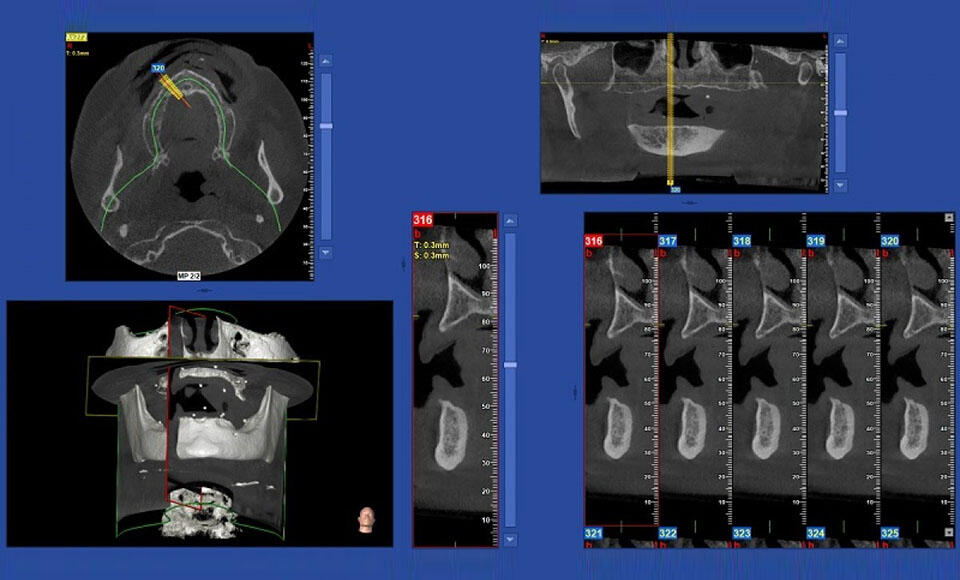

Vediamo un caso di un riabilitazione totale superiore su 8 impianti con carico immediato sviluppato partendo dalla Cone-Beam 3D NewTom GiANO HR Professional.

I tagli sono, infatti, lo strumento d’elezione per esplorare il volume acquisito e per effettuare misure accurate e certe.

Sapendo con certezza che un rendering non è un dato sul quale fare misurazioni: queste, infatti, vanno calcolate esclusivamente sulle ricostruzioni multiplanari. La conseguente esperienza acquisita ha cambiato profondamente il mio approccio verso la grande maggioranza dei casi che valuto e che, attraverso la comprensione e l’uso di questi dati, hanno un’asticella di difficoltà che si è progressivamente alzata sempre più. Questo spostamento in alto dei limiti non è controbilanciato dalla riduzione del coefficiente di rischio finale. Infatti, interventi prima neanche immaginabili oggi sono possibili. Quindi comunque alziamo anche l’asticella del rischio. Ciò sempre al fine di risolvere situazioni che per un paziente fanno la differenza tra una soluzione ad alto valore di confort post-operatorio, qualità della vita a guarigione avvenuta e fattibilità. Esiste anche un aspetto rilevante legato al fatto che possiamo trattare più pazienti.